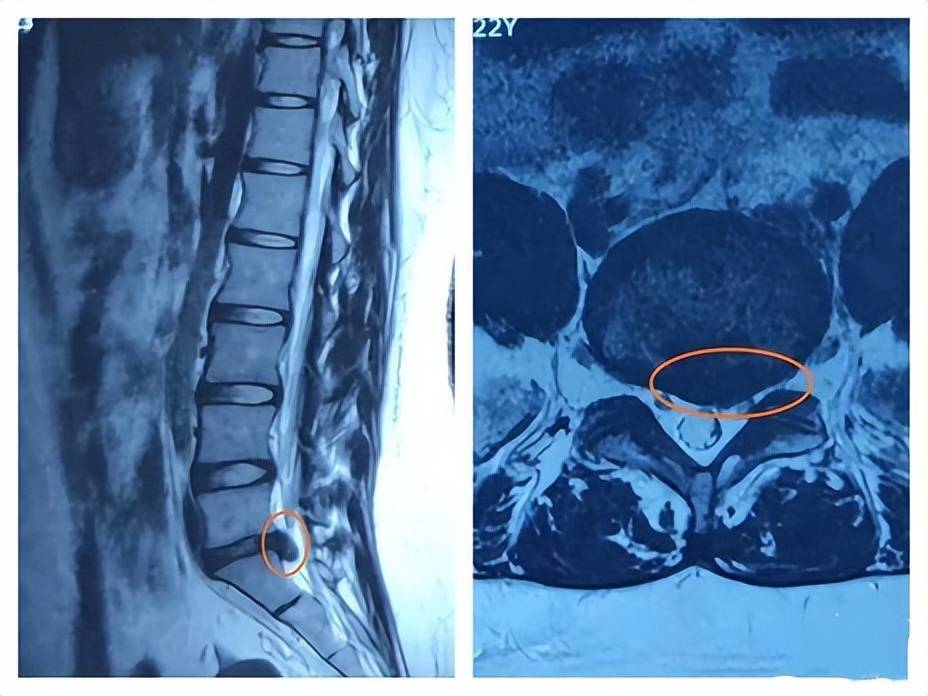

腰45椎间盘突出伴往上游离

术前mri显示巨大l45椎间盘向左后上方脱出